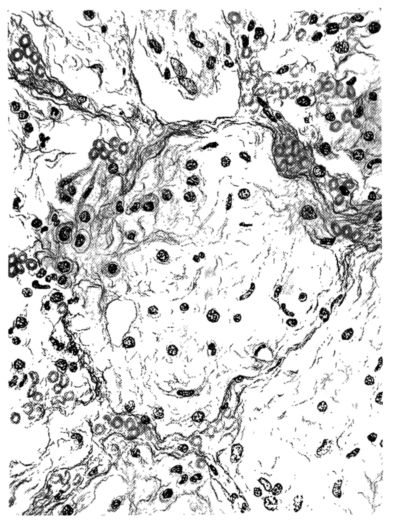

FIG. VII. AUTOPSY NO. 94. A NECROTIZING PROCESS LIKE THAT OF THE TRACHEA ILLUSTRATED IN FIGURE II. HERE IT IS SHOWN TO INVOLVE THE WALL OF THE BRONCHIOLE.

15There is considerable evidence to support the view that the disease spreads from bronchus to bronchus, and in keeping with this view, various stages in the inflammatory processes are more readily determined in these smaller structures than in the trachea. Furthermore, it must be emphasized that even the mildest and the most extreme of these stages are not infrequently encountered in the same lung. The earliest lesion is manifested by an increased homogeneity of the protoplasm of the epithelial lining of the bronchus. The cell protoplasm loses its normal granulation and the nucleus, somewhat darker than usual, becomes conspicuous on a red base (Fig. V). In the lumen of such a tube a serous exudate, perhaps mixed with mucus, is encountered, and there is some spreading apart of the surrounding muscular tissue with engorgement of the vessels. This picture merges gradually into one where the epithelium appears as a homogeneous, red-staining ribbon, devoid of nuclei, often exfoliated, in part at least, from the underlying submucosa (92). The change is traceable through the larger bronchi, even to the ducti alveolares, and not infrequently, bacteria, either as a diffuse, minute dotting or in the form of circumscribed, colony-like formations, are spread through the red, ribbon-like strand (Fig. XVI). With the exfoliation of the epithelial lining, the submucous vessels become more and more conspicuous and may bulge into the lumen of the tube (Fig. VI). That they actually weep into the lumen is proved by the presence of red blood cells in the exudate, now rich in mucus, broken-down nuclei, and desquamated cells. The necrotizing process may not extend deeper than the epithelial lining as is the status described above (140, 162), but it also frequently involves the underlying submucous and muscular layers, so that these lose their identity and stand out as homogeneous masses, in which fragmented nuclei and bacterial accumulations are prominent. Such deeper necrotizing areas may be focal (Fig. VII), or may involve the entire circumference of the tube (Fig. VIII). Occasionally, the epithelium, now dead and staining homogeneously, is lifted from the underlying submucosa in the form of a blister (66), and has very much the same appearance as the well known, early reaction which follows the application of croton oil to the rabbit’s ear. Where this occurs, the submucosa is less involved, as though the necrotizing agent had not penetrated to the same depth and the serous reaction beneath were actually a beneficent exudate. These blisters are in contrast with the deeper areas where the fibrinous mass, mixed with the dead tissue, forms an intensely staining ring or band, which extends through the bronchiolar wall even to the surrounding alveoli.